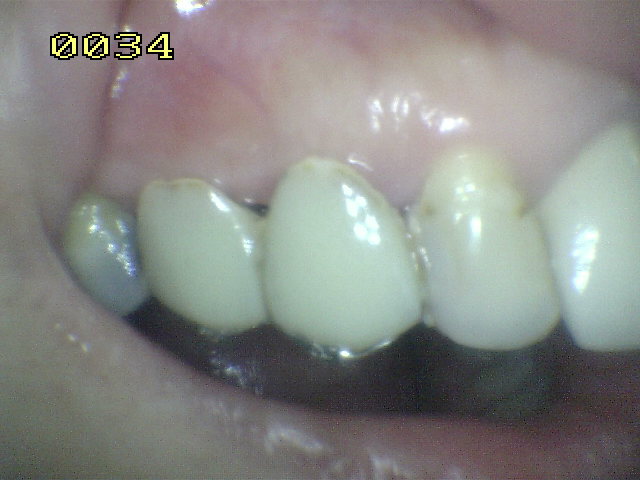

El material oscuro es una

amalgama cubierta por el diseño del puuente; observe los restos

de cemento adherido al esmalte dental.

Caries de esmalte y dentina

en el otro pilar (flechas rojas)